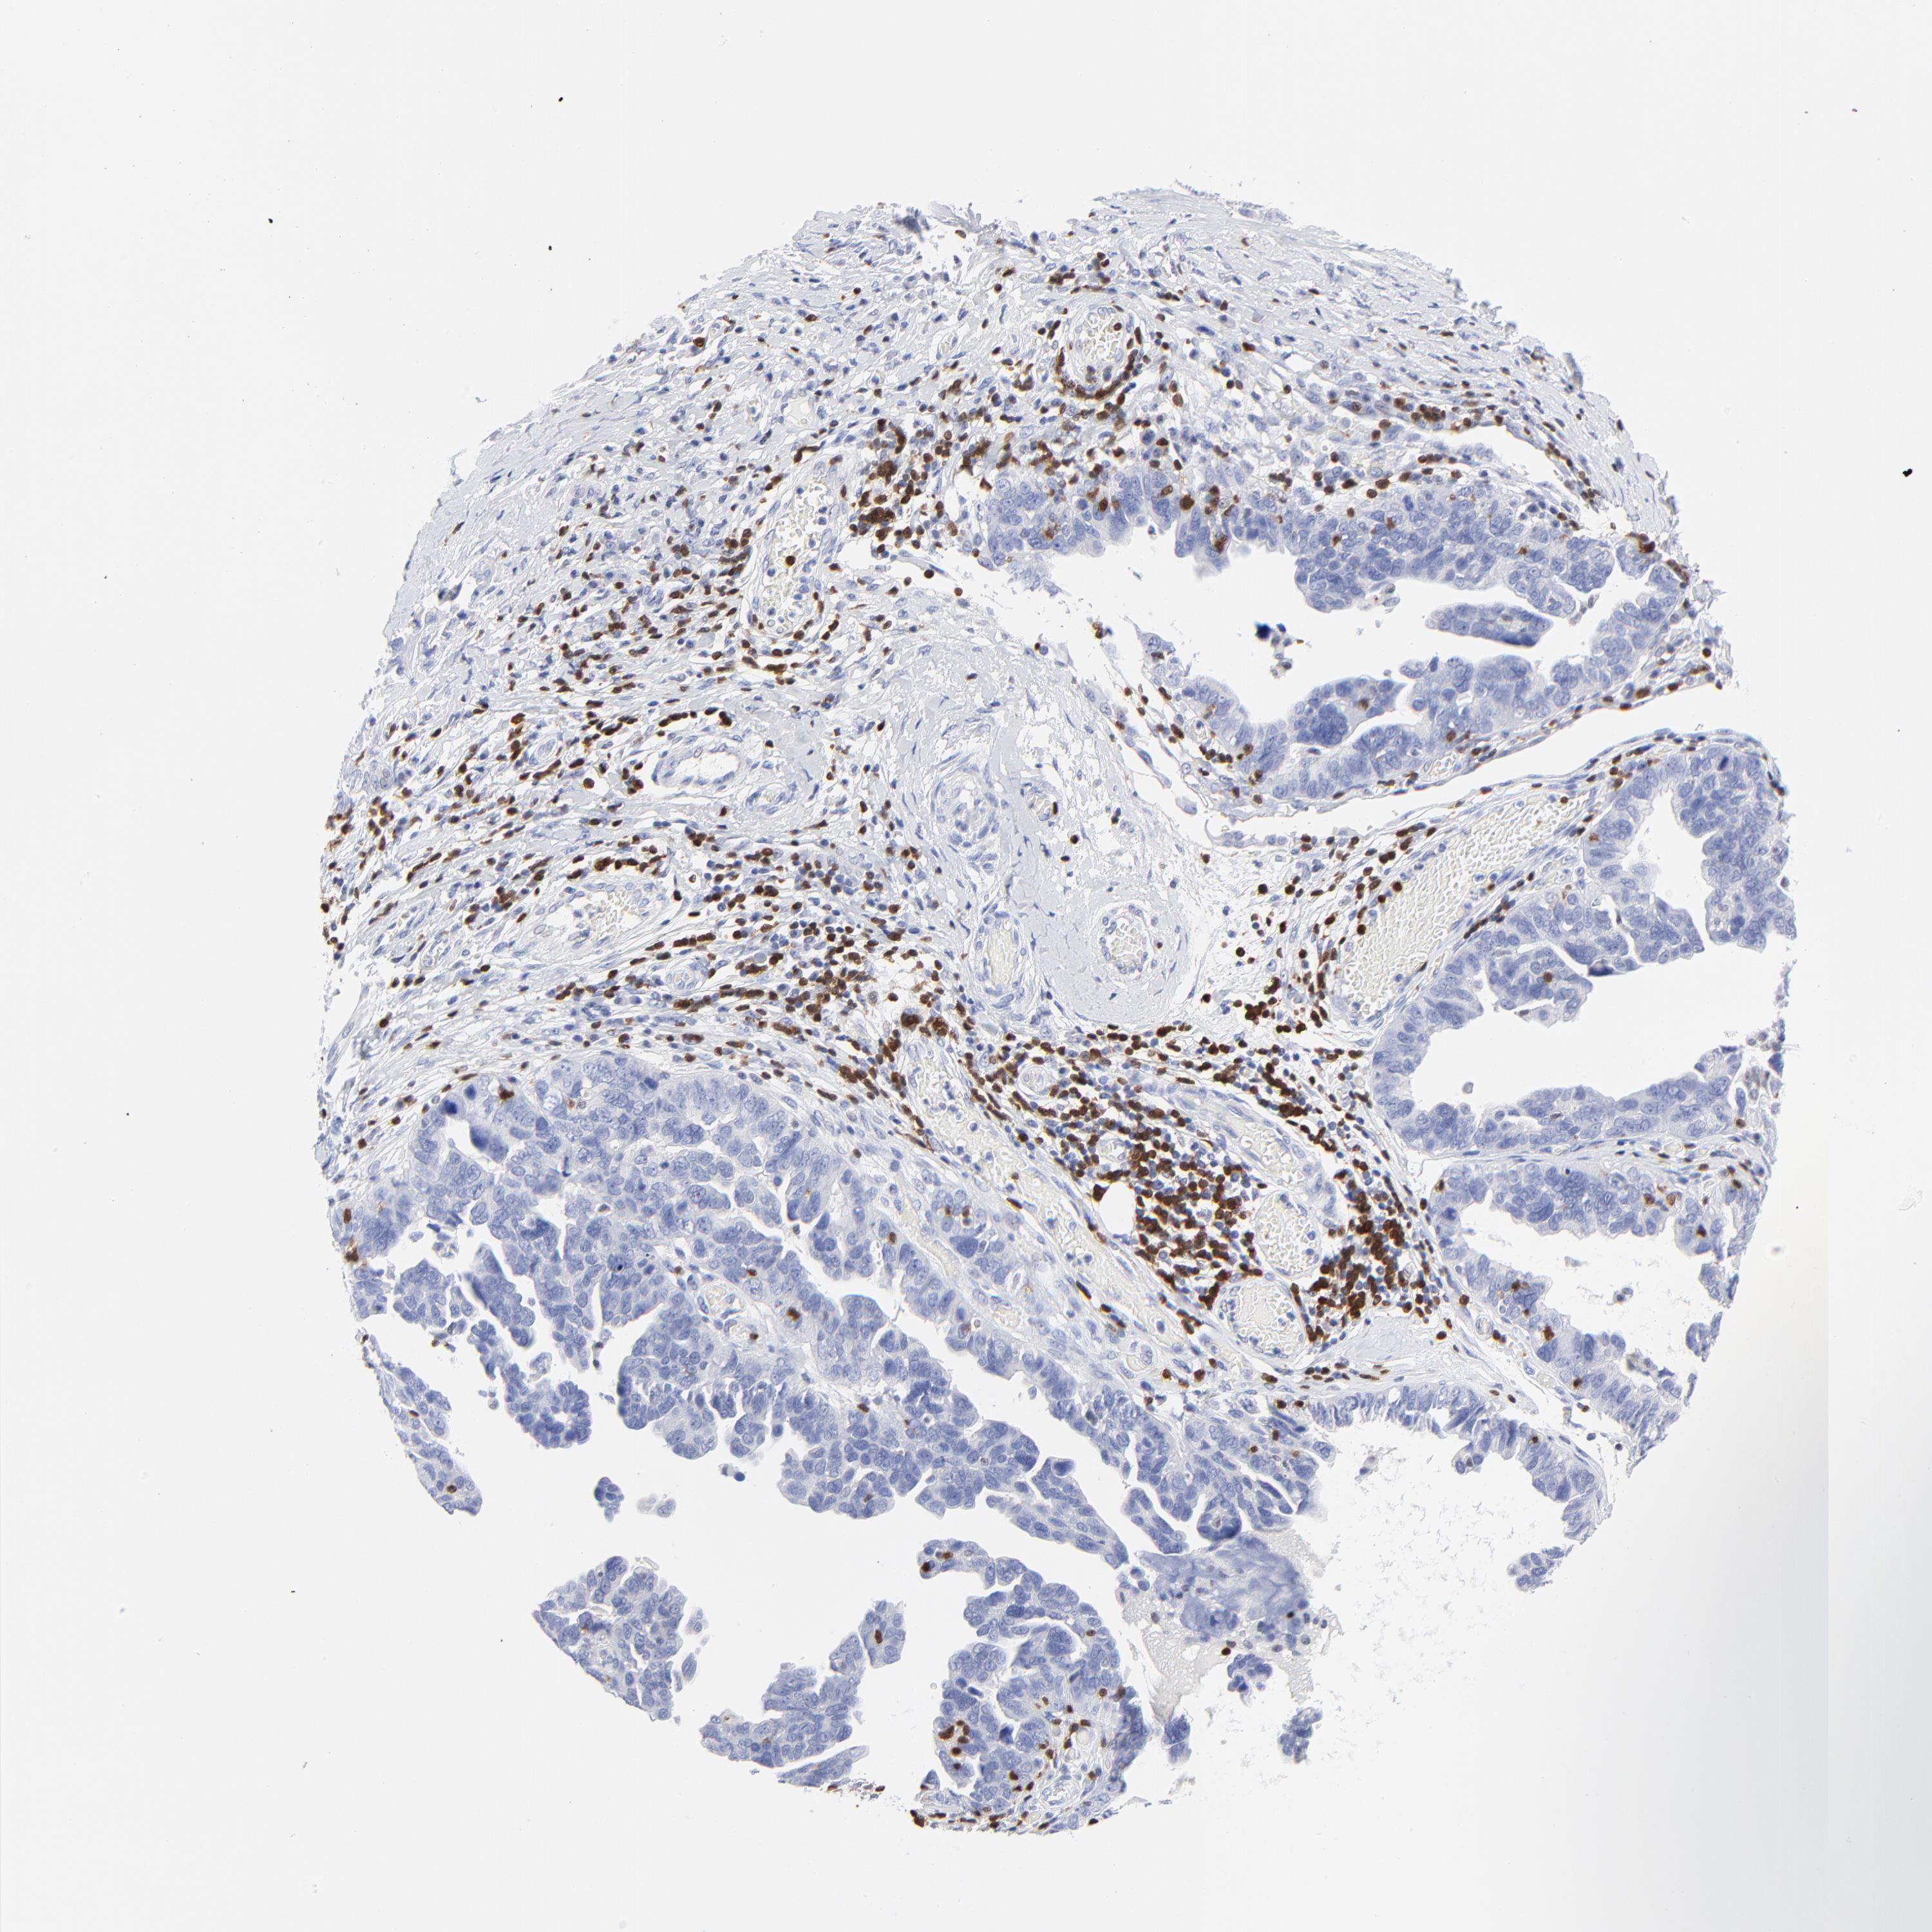

OVARIAN CANCER - Protein expressioni

A mouse-over function shows sample information and annotation data. Click on an image to view it in a full screen mode. Samples can be filtered based on level of antibody staining by selecting one or several of the following categories: high, medium, low and not detected. The assay and annotation is described here.

Note that samples used for immunohistochemistry by the Human Protein Atlas do not correspond to samples in the TCGA dataset.

Antibody stainingi

Antibody staining in the annotated cell types in the current human tissue is reported as not detected, low, medium, or high, based on conventional immunohistochemistry profiling in selected tissues. This score is based on the combination of the staining intensity and fraction of stained cells.

Each image is clickable and will lead to virtual microscopy that enables deeper exploration of all samples and also displays staining intensity scores, fraction scores and subcellular localization as well as patient and tissue information for each sample.

Antibody HPA003134

Antibody CAB002625

Staining

High

Medium

Low

Not detected

Intensity

Strong

Moderate

Weak

Negative

Quantity

>75%

75%-25%

<25%

None

Location

Nuclear

Cytoplasmic/membranous

Cytoplasmic/membranous,nuclear

Cystadenocarcinoma, mucinous, NOS

Carcinoma, endometroid

Cystadenocarcinoma, serous, NOS